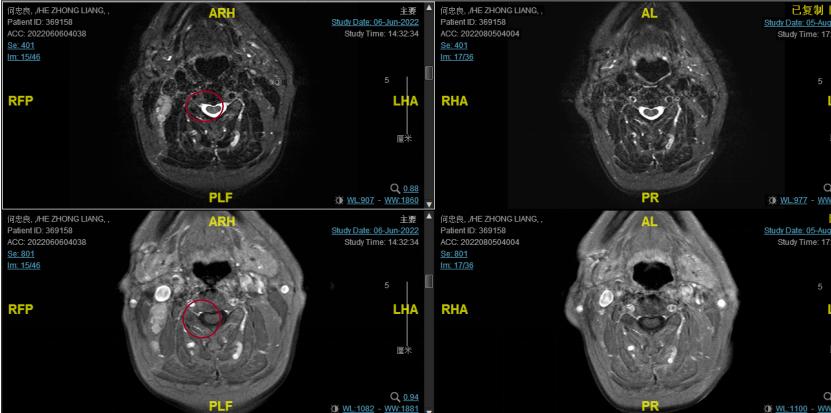

2022-06-29行鼻咽IGRT放疗:GTV1 68Gy/32f 、GTV2 68Gy/32f、CTV1 60Gy/32f、CTV2 50.4Gy/28f。期间同步斯鲁利单抗+尼妥珠单抗+恩度治疗。

▌疗效评估

2022-08-05(放疗近结束)复查MR, 疗效评价:CR。鼻咽部肿物及咽后转移淋巴结颈部转移淋巴结均达到CR。